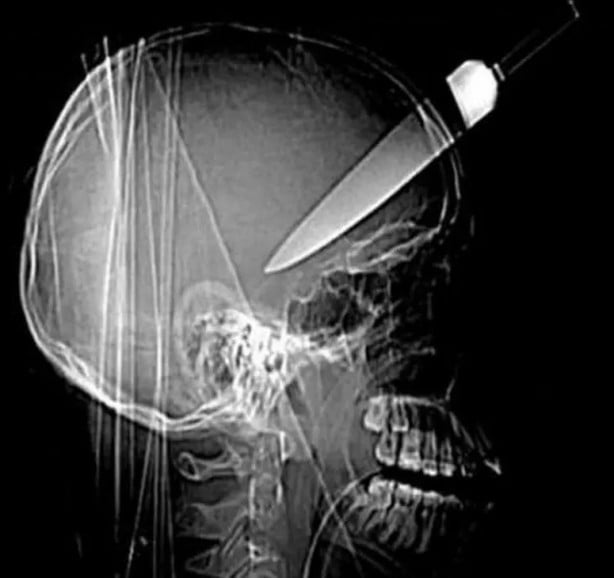

Hepsi birbirinden korkunç! Doktorları bile şaşkına çeviren görüntüler

İşte doktorları bile dehşete düşüren dünyanın en tuhaf röntgen filmleri...